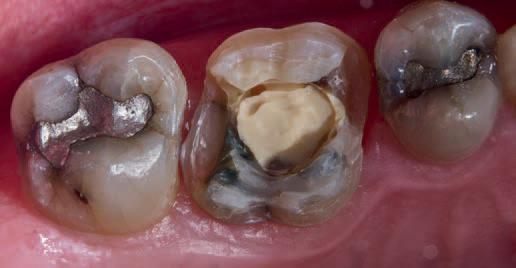

As the plan was to restore the tooth with a full- coverage indirect restoration, the entire pulp cavity was filled with Biodentinee™ with the Bio-Bulk Fill technique. (Fig. 9).

The patient returned after twelve weeks and reported that the tooth had been asymptomatic (Fig. 10). At this appointment, a preparation for a ¾ crown was performed (Fig. 11). The Biodentinee™ was left in situ, cut back and used as a core for the restoration. A PVS impression was recorded, and a BISAcrylic temporary crown cemented with provisional cement (Fig. 12).

Fig. 10: Tooth at 12-week review.

Fig. 9: Cavity filled with Biodentinee™.